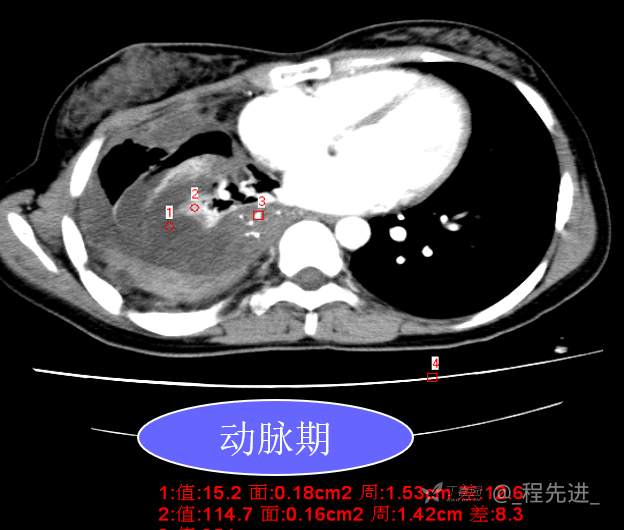

患者性别:女

患者年龄:26岁

简要病史:反复胸闷、气喘、咳嗽半年